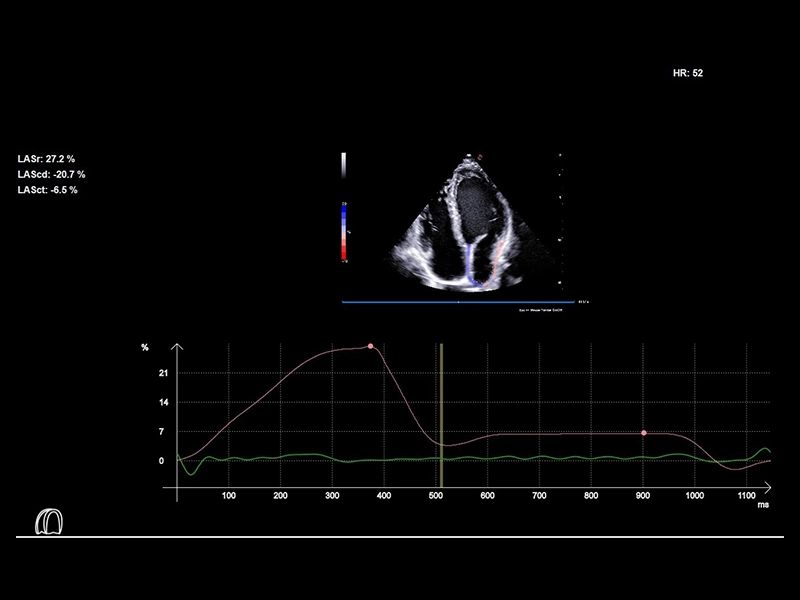

MyLab™E80 - XStrain LA

MyLab™E80 - XStrain LA